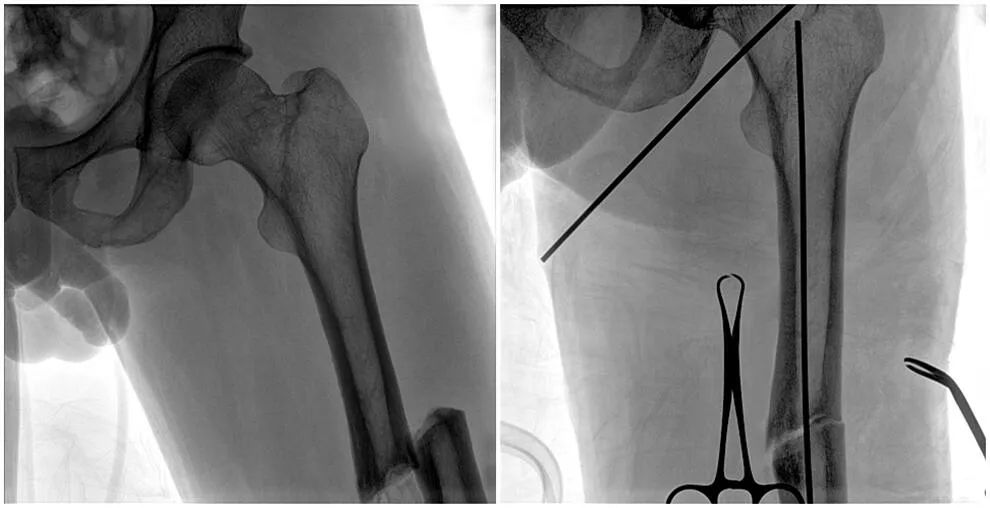

C形臂輔助手術(shù)過程

術(shù)中使用普愛醫(yī)療大平板一體式C形臂進(jìn)行透視,判斷骨折情況及克氏針、髓內(nèi)釘?shù)冉饘僦踩胛锏奈恢茫M(jìn)行調(diào)整。C形臂準(zhǔn)確的術(shù)中定位,大大縮短了手術(shù)的時(shí)間,減輕了患者的痛苦,輔助手術(shù)順利完成。

在進(jìn)行髓內(nèi)釘內(nèi)固定術(shù)時(shí),醫(yī)生需要同時(shí)觀察到入釘點(diǎn)和骨折部位的情況,普愛醫(yī)療大平板一體式C形臂采用30CM×30CM的平板探測(cè)器,能夠呈現(xiàn)更廣闊的成像面積,滿足大部分長(zhǎng)骨髓內(nèi)釘內(nèi)固定術(shù)的攝片需求。

術(shù)中定位準(zhǔn)確、出血量少,術(shù)后影像顯示股骨移位糾正,恢復(fù)良好力線,手術(shù)效果良好。